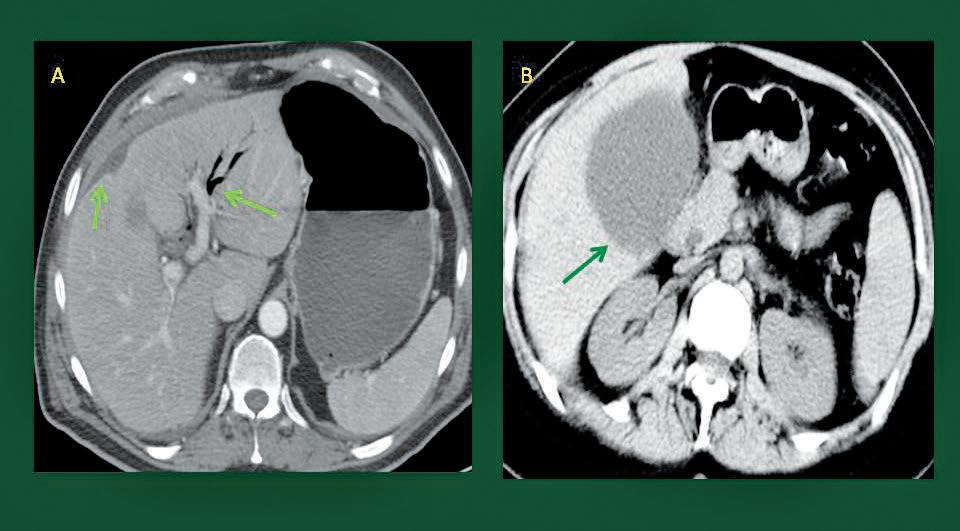

La paciente de alrededor de 40 años bajó a rayos X para hacerle un estudio en el que queríamos saber si había mejorado el biloma que se le había producido posterior a una cirugía de vías biliares. Un biloma es una colección de líquido biliar, con frecuencia encapsulada, que resulta de la fuga de bilis en alguno de los segmentos de los conductos biliares.

Yo era el residente de tercer año encargado del sector de internamiento. El estudio se realizó sin problema y se observó que la colección había reducido. Sin embargo, en menos de una hora de que la paciente regresó, desarrolló el choque séptico más feroz y rápido que había yo visto en mi entonces, aún corta experiencia profesional. La temperatura subió a 40 grados y en menos de 15 minutos la presión arterial había caído considerablemente. 80/50 dijo la enfermera después de la toma inicial. Era un cuadro de colangitis (infección de las vías biliares), muy grave, que había detonado la producción de un choque circulatorio.

Fuga biliar y bilioma. Foto: Envatoelements